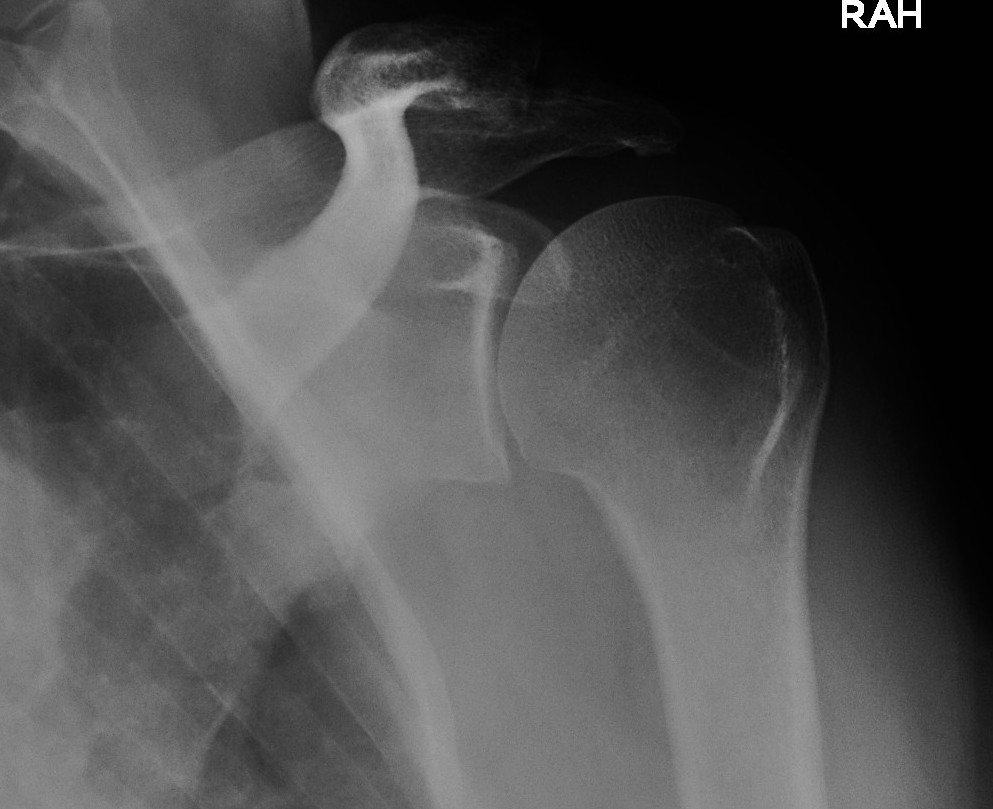

AP Shoulder

Technique

- in plane of thorax

- oblique of GHJ